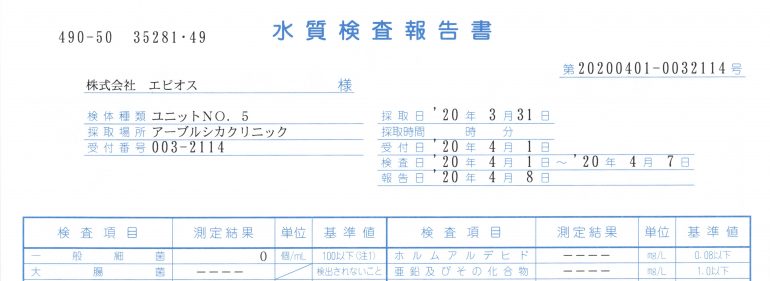

アーブル歯科クリニックでは習志野市で初めて、エピオスエコシステムを導入し水道水ではなく、殺菌水で、虫歯治療や歯のクリーニングをしています。

毎年必ず、水質検査を行い、治療水が汚染していないか確認しています

水を出す大元から一番遠い歯科ユニットの水質検査をしても治療水から細菌は検出されませんでした

つまり、すべての歯科ユニットの治療水から細菌が検出されないということになります

歯科治療水安全認定施設賞証を6年連続で獲得。

飲んでも安全で清潔な治療水として認定されています。